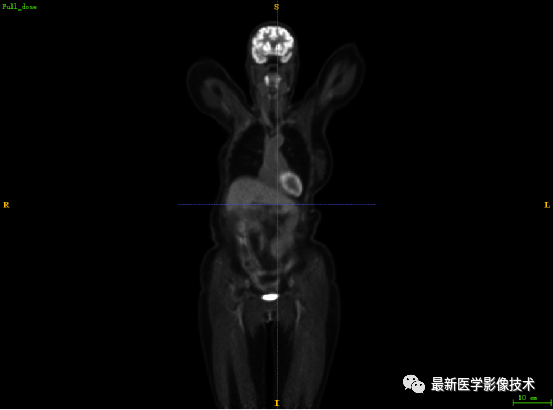

7.1、低剂量2重建结果

第一张是低剂量2的PET图像,第二张是full剂量PET图像,第三张是网络重建的PET图像。